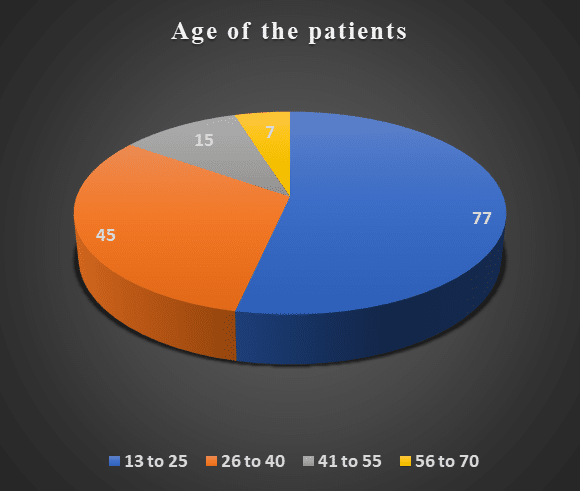

Evaluating the Clinical Presentation of Acute Abdominal Pain in the Emergency Room at a Tertiary Care Hospital in Pakistan: A Cross-Sectional Study

Background: Acute abdominal pain (AAP) is a significant clinical issue globally, contributing to approximately 7-10% of emergency room (ER) visits....Read More